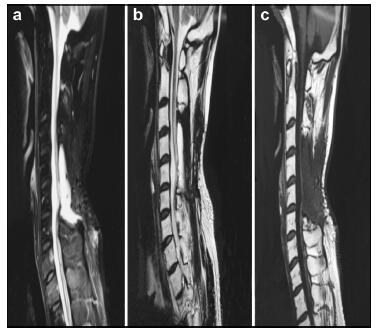

20170512093634  Figure 1 a–c. Preoperative MR images of Case 1.